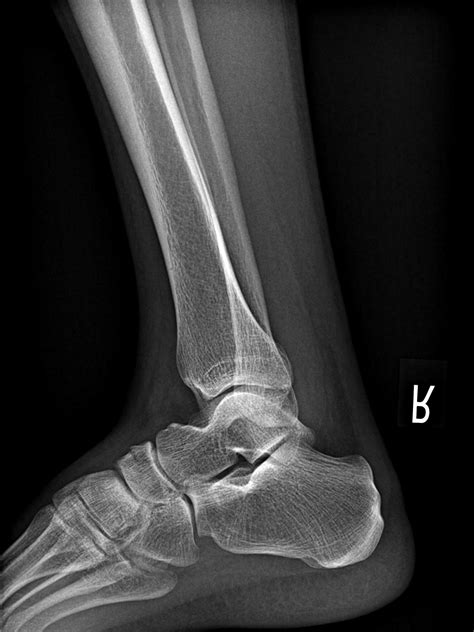

X-ray Imaging Primary scan to identify major breaks or displacement.

MRI or CT Scan Used for occult fractures that are hidden on standard X-rays.